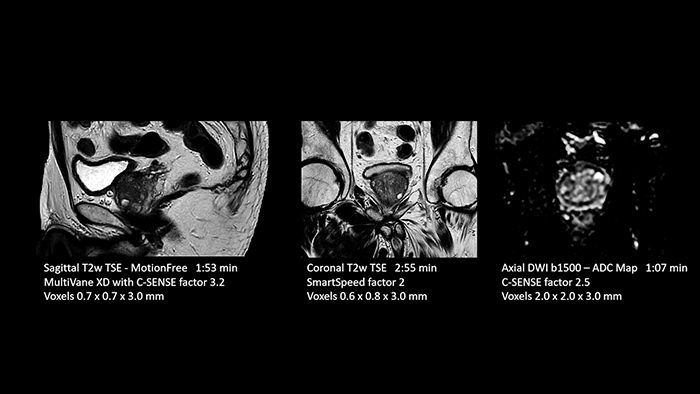

“Thanks to SmartSpeed, we are able to perform examinations extremely quickly. We can carry out most examinations in under ten minutes. Our MRI exam of the knee only takes six minutes. The shorter time makes it easier for patients to lay still, which helps prevent motion artifacts. Dr. Schröter also highlights their step forward in MRI of the prostate. “In prostate exams we have saved almost 50 percent of time. We used to need about 35 minutes for an MRI exam of the prostate and now we can do it in just 18 minutes with a significantly higher resolution and higher image quality.”

Dr. Schröter points out that a more confident diagnosis requires high-quality images with more diagnostic information. “Philips SmartSpeed provided that to us. AI denoises the clinical images without losing any important data, resulting in high-resolution images. It keeps all the information we need and makes the images better. We can apply SmartSpeed to almost all sequences. That is a big step forward! We use it for example in 3D imaging and in diffusion-weighted imaging, to dramatically reduce scan time or increase image resolution, which is quite useful. There are small lesions that we would certainly have seen without SmartSpeed, however it would have taken us longer to properly diagnose. In 3D MSK images with extremely high resolution, we uncover the finest anatomical structures and can thus report very detailed findings.”

With SmartSpeed also scan times for diffusion imaging and motion-free imaging can be reduced. Scanned without contrast agent. Performed with 1.5T Ambition X, dS Torso coil.